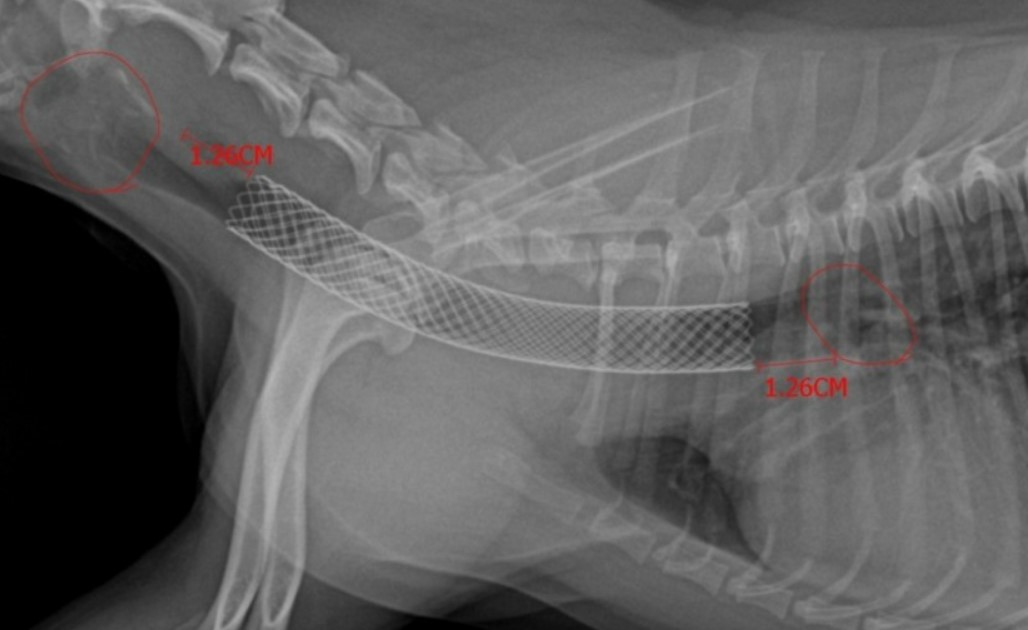

개가 숨을 쉬는 동안 X 선을 찍으면 때로는 기관이 무너지고 있음을 보여줄 수 있지만

형광 투시 (모바일 X 선의 일종) 또는 기관지 내시경 (튜브 끝에 작은 비디오 카메라가있는 튜브 삽입)과 같은

더 많은 진단 테스트가 가능합니다.